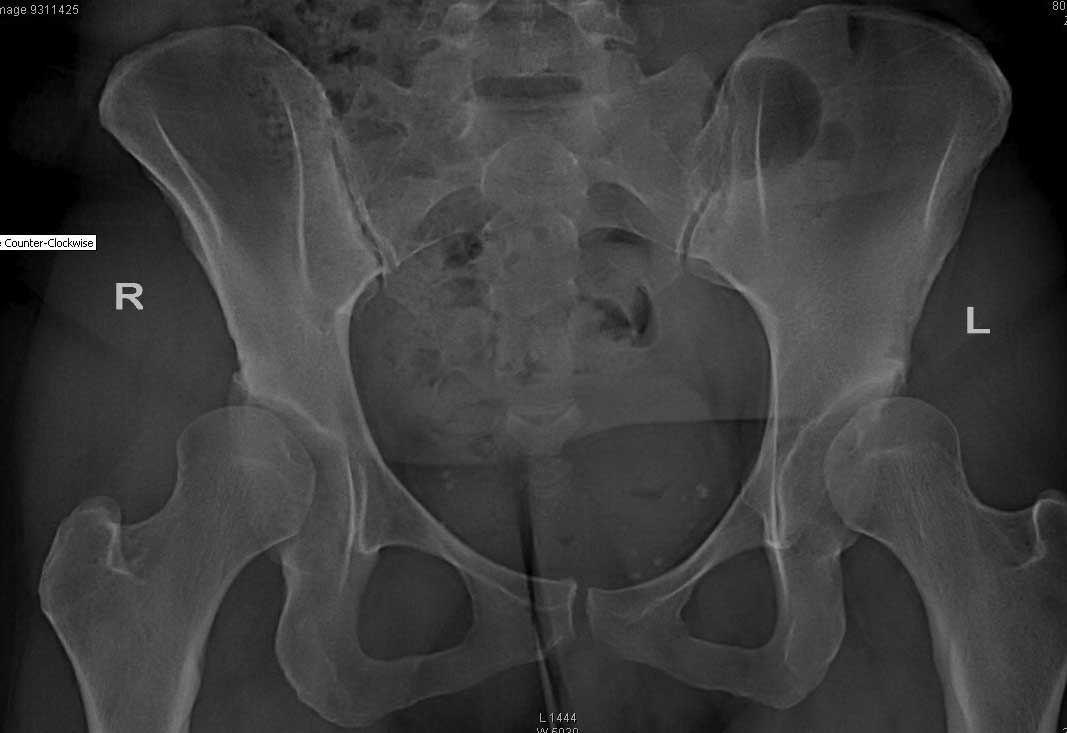

Пациентке 31 год. Р-гр прилагаю. Житель ЕС. консультировалась в Германии,Франции и Италии. могут выполнить протезирование но советуют поискать специалистов, занимающихся остеотомиями таза.